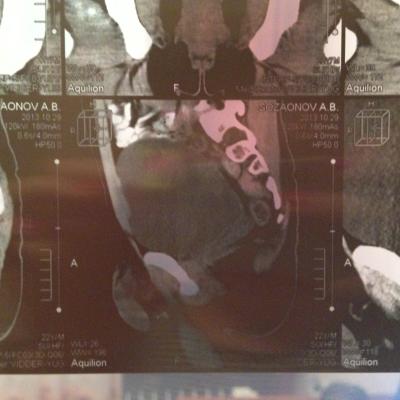

Семенные пузырьки-конфигурация не совсем типична,примерный размер правого 26*28мм.Отмечаются признаки кистовидной трансформации и микрокальцинации обоих пузырьков.Наибольшая из кист слева достигает 9 мм.Обращает на себя внимание неравномерная кальцинация стенок крупных регионарных(текстикулярных)артерий с обоих сторон.

Заключение:на момент исследования,КТ-данных за наличие внеорганных дополнительных патологических образований,лимфоденопатии или свободной жидкости в области таза не выявлено.КТ-признаки в пользу проявлений калькулезного везикулита с элементами кистовидной трансформации семенных пузырьков.